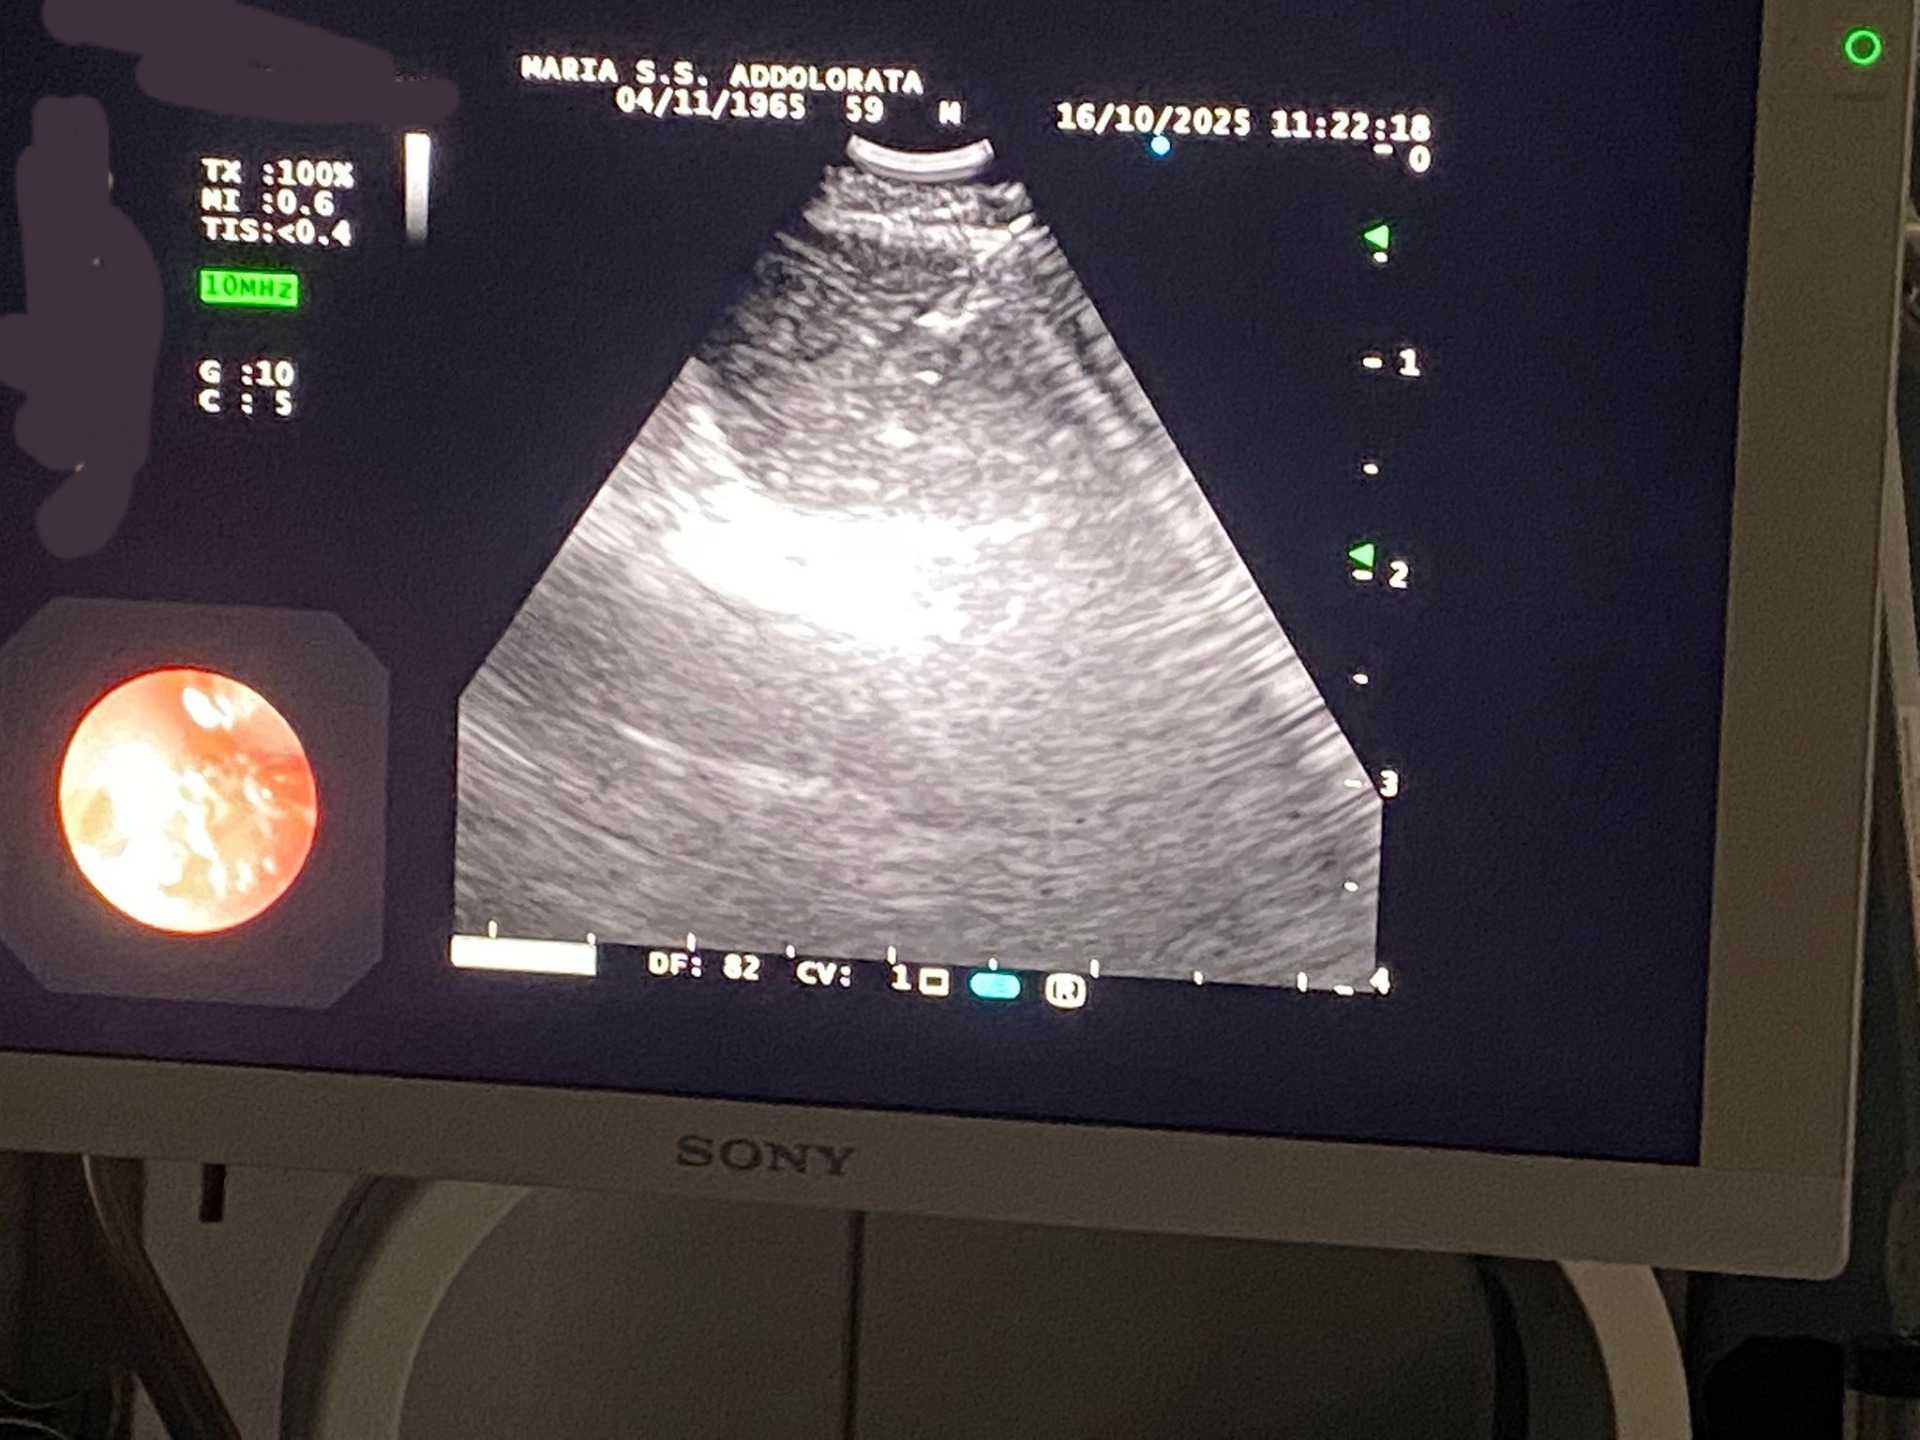

**Primo Procedimento a Eboli** Il 16 ottobre 2025 si è effettuata ad Eboli la prima procedura di CP-EBUS secondo gli standard nordamericani, condotta dal Dott. Damiano Capaccio (Direttore della Pneumologia Interventistica) e dalla Dott.ssa Alessandra Cotroneo (Dirigente Medico) per la stadiazione dei linfonodi mediastinici con guida CP-EBUS- La procedura è stata effettuata nella nuova sala di endoscopia toracica seguendo i criteri suggeriti dal documento nordamericano. L'intervento è stato garantito dall'anestesista di sala dott. Paolo Russo coordinato dal Direttore del Dipartimento dell'ASL. Dott. Fernando Chiumiento. - È stata seguita in sala dagli infermieri professionali Sonia Mastrolia, Anna Zinna e Nunzia Sannino. - In sala presente il dott. Carmine Guarino, gia' Direttore della Endoscopia Toracica dell'Ospedale Monaldi di Napoli.

Giovedi scorso nella sala di endoscopia toracica del Presidio Ospedaliero di Eboli, è stata attuata una nuova procedura che permette di biopsizzare i linfonodi del mediastino. Essa è di rilevante importanza nella stadiazione del tumore del polmone ( la metodica utilizza un broncoscopio con sonda guida ecografica ( ecobroncoscopio) che permette di evidenziare i linfonodi sospetti di metastasi in tempo reale e biopsizzare con ago ( TBNA a guida EBUS).Chiaramente la metodica viene utilizzata anche per la diagnosi di altre patologie quali linfoma, sarcoidosi , TBC. La procedura si effettua in anestesia e quindi necessaria la presenza di anestesista, 2 medici pneumologi e 3 infermieri. Al momento siamo l'unica struttura operativa in provincia di Salerno---"Pubblicazione e Novità Scientifiche (4 ottobre 2025)"